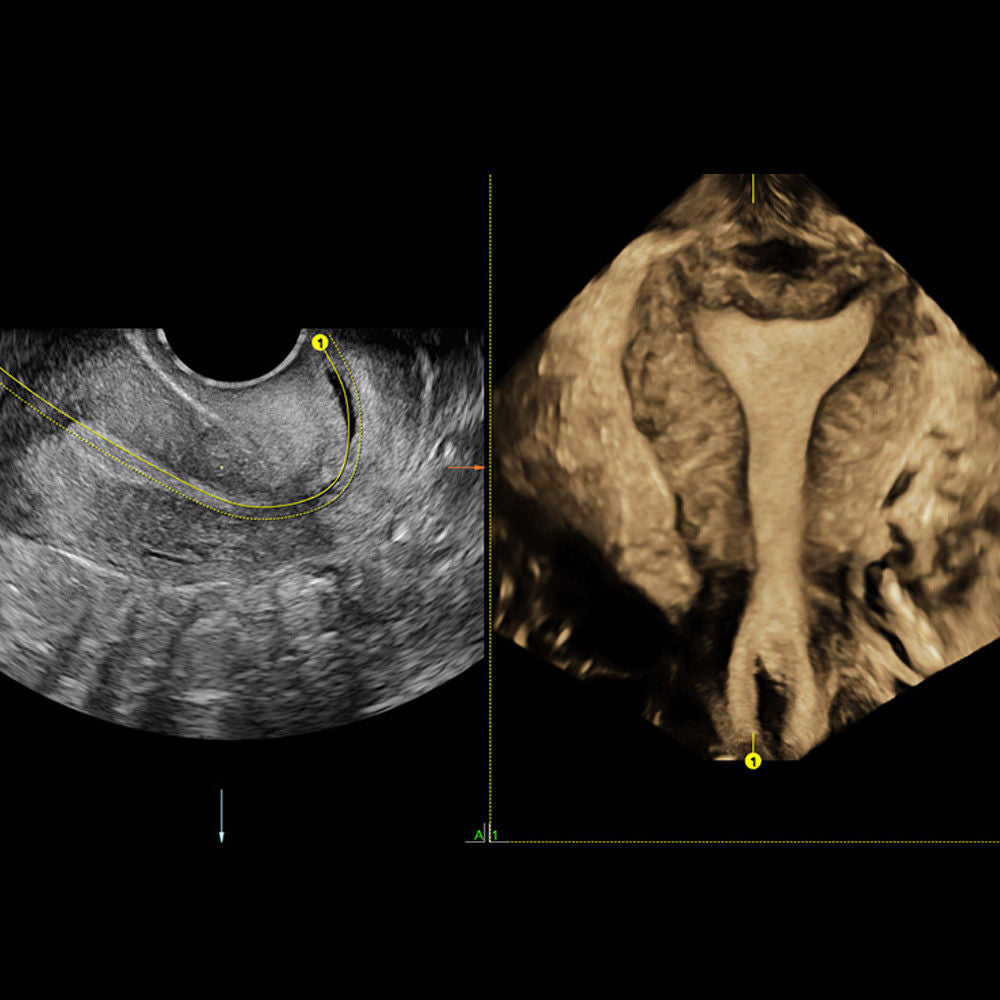

Brand: HD LIVE 4D

MPN: 4DHDLIVE-RAB6-D-SYSTEM-VOLUMETRIC-CONVEX